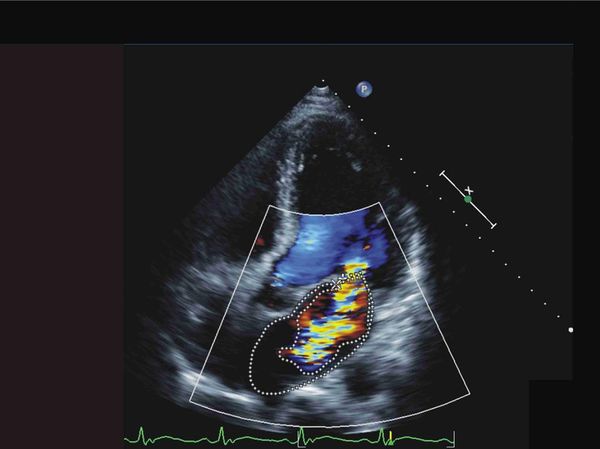

▲患者心臟有明顯雜音,可能有內膜炎造成的問題。(圖/彰基提供)

陳姓果農旋即被宣告病危,送入加護病房。在馬拉松式的照護下,緊急心臟超音波檢查揭示二尖瓣的嚴重閉鎖不全,血液培養不到8小時就長出金黃色葡萄球菌,顯示心臟深受感染,讓醫療團隊震驚不已。彰基心臟外科主任醫師陳映澄緊急會診後,決定進行微創二尖瓣人工瓣膜置換術。